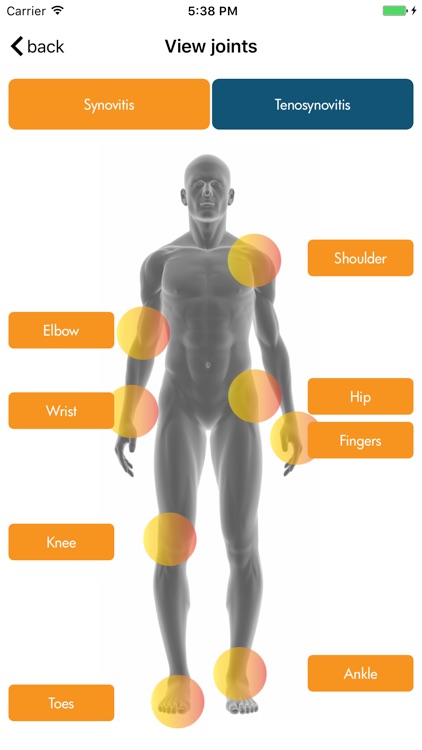

Ultrasound detected synovitis is a powerful imaging tool used worldwide that helps diagnose, monitor and treat patients with rheumatoid arthritis . RAUSSA application has been developed to help you score joint and tendon ultrasound grey scale and Doppler detected synovitis while performing your ultrasound examination. RAUSSA is made-up of almost 400 images from patients with rheumatoid arthritis. Takes no more than 2 minutes to learn! In every area you can look at a representative anatomic specimen image, up to 4 different US images with the same grey scale or Doppler mode score. , Dr. J. Uson MD PhD , Dr. I. Möller MD PhD and Dr. E. Naredo MD PhD, experts in rheumatologic ultrasound have obtained the images in this app.

Ultrasound detected synovitis is a powerful imaging tool used worldwide that helps diagnose, monitor and treat patients with rheumatoid arthritis . RAUSSA application has been developed to help you score joint and tendon ultrasound grey scale and Doppler detected synovitis while performing your ultrasound examination. RAUSSA is made-up of almost 400 images from patients with rheumatoid arthritis. Takes no more than 2 minutes to learn! In every area you can look at a representative anatomic specimen image, up to 4 different US images with the same grey scale or Doppler mode score. , Dr. J. Uson MD PhD , Dr. I. Möller MD PhD and Dr. E. Naredo MD PhD, experts in rheumatologic ultrasound have obtained the images in this app.